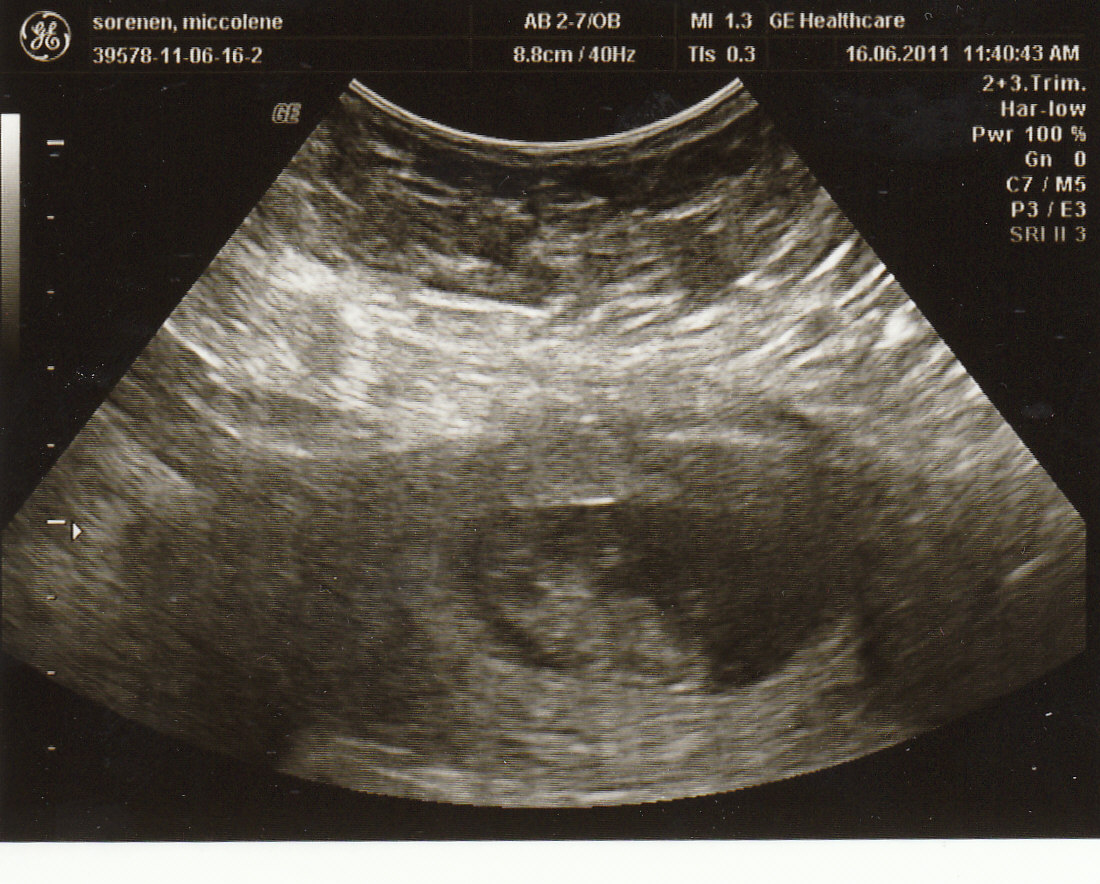

But this Father’s Day we’ve got big news-